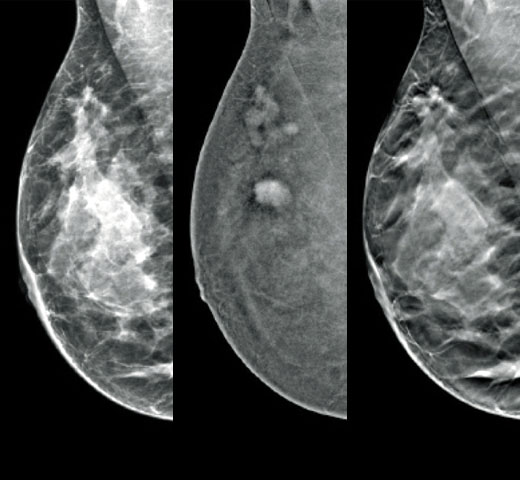

Images cliniques

Images cliniques d’une mammographie

Images cliniques d’une mammographie avec lésion suspecte

Images cliniques d’une mammographie sur un sein graisseux